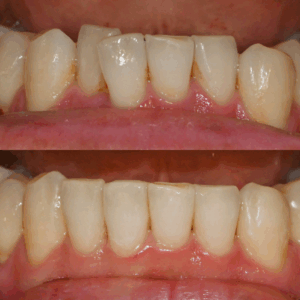

임플란트 를 심고 싶은데 공간이 부족하다면? 비발치 치아 교정

안녕하세요, 교정과 전문의 김정은입니다. ​ 이가 빠지거나 부러졌을 때, “임플란트를 심어야겠다"라는 생각을 하시는 분들이 많습니다. ​ 그런데 실제로 내원해 검사해 보면, 이가 없던 자리에 인접치가 쓰러지거나 공간이 부족해져 있어, 픽스처를…